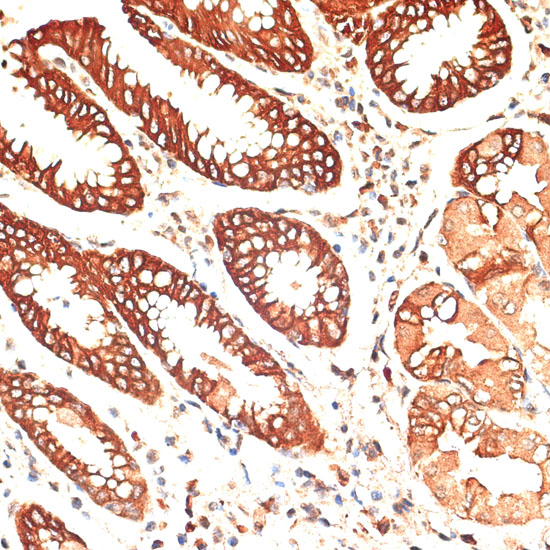

Immunohistochemistry of paraffin-embedded human stomach using KRT13 at dilution of 1:100 (40x lens).